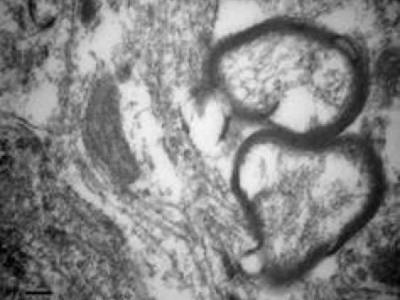

电镜下(× 3 500)见给予胺碘酮的新生鼠海马组织微管排列紊乱 最近的研究发现,全...